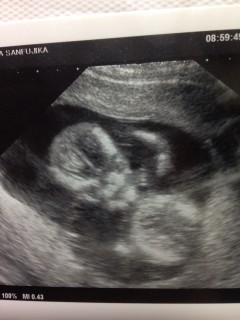

二週間ぶり4回目の検診です。 サイズはアタマからおしりまでで5.5センチ。順調だそうで一安心^^ 左手をグーパーして、アタマをぽりぽりかいてるのが見れました!小さなおててが本当にキュート!正面からの写真でなんだか笑ってるみたいでこっちまで顔が緩みます^^